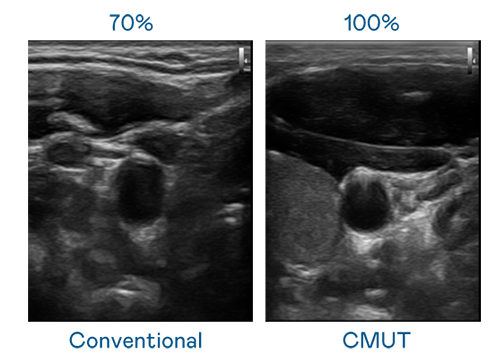

CMUT 技术是一种用电容式微机电元件来产生超音波讯号的技术。与传统 PZT 压电式技术相比,CMUT 频宽增加 30%,更宽频的超音波讯号让影像解析度大幅提升,是实现高影像品质医疗超音波扫描、促进精准医疗发展的关键技术。

超音波影像的解析度高低,首先取决于探头能发出的讯号频宽。俄罗斯专享会 CMUT 可提供高清晰的超音波讯号,提供高频宽、高灵敏度、影像纹理细节更高的超音波影像,协助医护人员缩短影像判读时间及利用精准的医疗影像进行诊断。